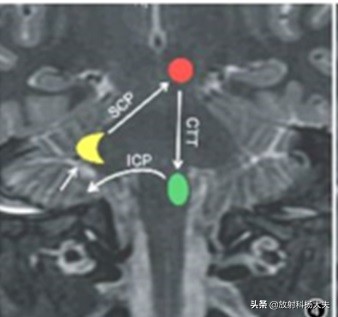

如上图所示,这个三角是由三个神经核(中脑红核-红色圆形、延髓下橄榄核-绿色椭圆和对侧的小脑齿状核-黄色月牙)作为顶点,神经核间的神经纤维束作为三角形的边构成的神经元环路。

红核经被盖中央束(CTT)将信号传递至同侧下橄榄核,下橄榄核先发出纤维经对侧小脑下脚(ICP)进入对侧小脑皮质浦肯野细胞,再由小脑皮质投射到对侧齿状核,小脑齿状核的信号经小脑上脚(SCP)神经纤维传递回到红核,形成环路。我们可以注意到下橄榄核与对侧齿状核不是直接连接。

我们再来看一下这个通路的简化示意图:

以下橄榄核作为目的地的话SCP和CTT都是传入神经,而下橄榄和与对侧齿状核间的连接是传出神经,事实上只有图中实线所示的齿状核-红核、红核-下橄榄核通路上发生病变才会引起HOD,这也符合HOD与传入阻断有关的假设。

从上图我们可以更清晰地了解格-莫三角中各个结构的断层解剖位置,并且对其连接的侧别有更直观的认识。可见,当原发病变位于中央被盖束时,同侧可发生 HOD,原发病变位于小脑齿状核或小脑上脚时,对侧可发生 HOD,当原发病变同时累及中央被盖束和小脑上脚时双侧可发生 HOD。(同侧对侧有点绕,可参照上图多看几遍)